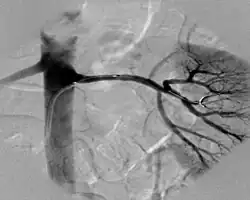

Eine Dopplerultraschalluntersuchung der Nierenarterien kann diese in 88 % der vorliegenden Fälle erkennen und in 89 % der nicht-vorliegenden Fälle ausschließen. Eine Magnetresonanztomographie-Untersuchung (MRT) der Nierenarterien oder eine Computertomographie leisten dies mit einer Sensitivität und Spezifität von jeweils mehr als 94 %. Der Goldstandard der Diagnostik ist eine intraarterielle digitale Subtraktionsangiographie (i. a. DSA), bei der durch eine Punktion der Leistenarterie ein Katheter in die Nierenarterie eingebracht wird, um diese direkt durch Kontrastmittelfluss sichtbar zu machen. In den bildgebenden Verfahren kann eine arteriosklerotische Engstelle von einer fibromuskulären Dysplasie abgegrenzt werden.[2]